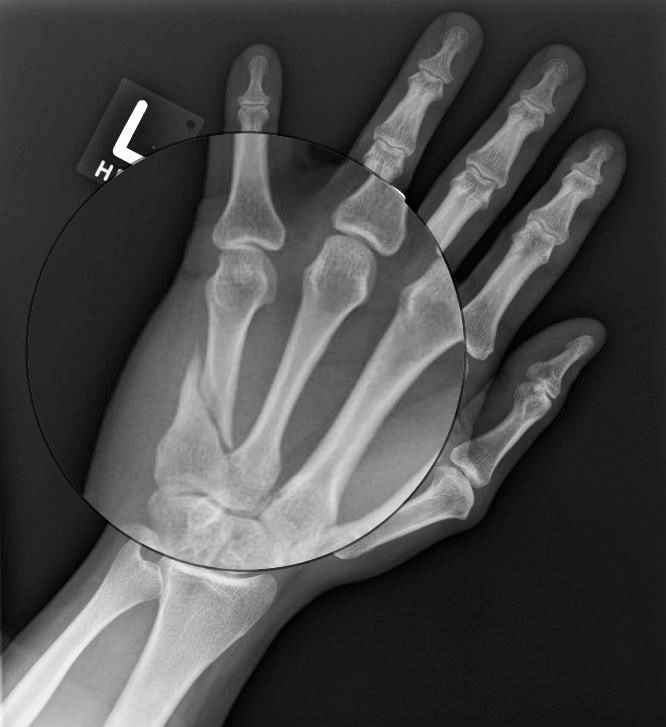

Hand Fracture Raleigh Hand Surgery — Joseph J. Schreiber, MD How Does A Spiral Fracture Heal  Typically, a spiral fracture in the fibula takes around 3 to 6 months to heal fully. Treatment can depend on the severity of the breakage, but may include surgery. The force results in a twisting or spiral break in the bone. You may need to wear a medical boot or cast for. Can a spiral fracture heal completely without surgical. How Does A Spiral Fracture Heal.

Hand Fracture Raleigh Hand Surgery — Joseph J. Schreiber, MD How Does A Spiral Fracture Heal  A spiral fracture occurs when one end of a bone remains in place while the other end is in motion. You may need to wear a medical boot or cast for. A spiral fracture is a bone fracture that occurs when a long bone is broken by a twisting force. How long it takes to heal a spiral fracture depends. How Does A Spiral Fracture Heal.